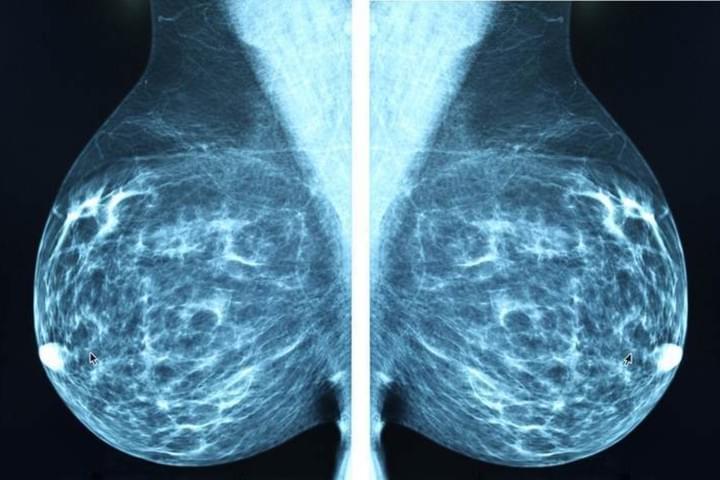

Computational radiology for cancer

Precision mammography

Over 250,000 women will be diagnosed with breast cancer this year alone, but at least five million will be incorrectly screened by mammography and recalled for additional testing. To realize precision oncology for breast cancer screening, we train, optimize, and validate powerful deep learning algorithms on almost 5 million digital mammograms to more accurately detect clinically significant cancer, reduce anxiety from false positive screening, and decrease morbidity of unnecessary downstream procedures. Improved precision in screening for breast oncology may help tip the balance of routine screening towards greater benefit and less harm for millions of women.